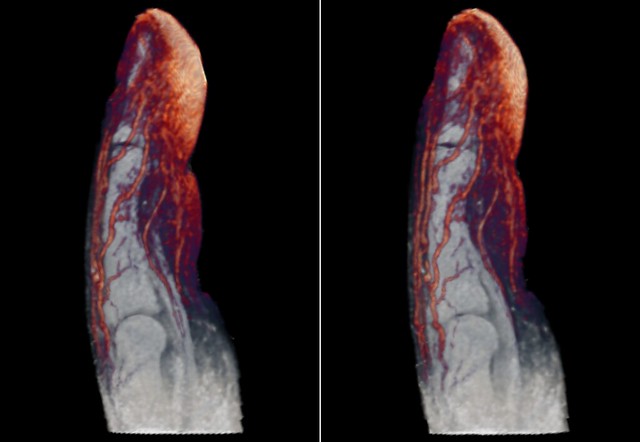

16. Кровоносні судини пальця. Ось чому починає текти кров, варто лише трішки порізати палець